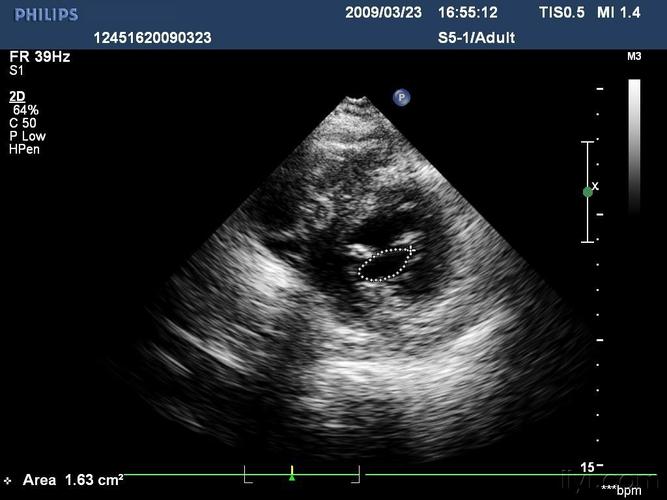

2·m型超声心动图 (1)梗阻者二尖瓣c‐d段呈多层弓背样隆起,称为sam

肥厚型心肌病sam征图片

sam征超声心动图

超声心动图